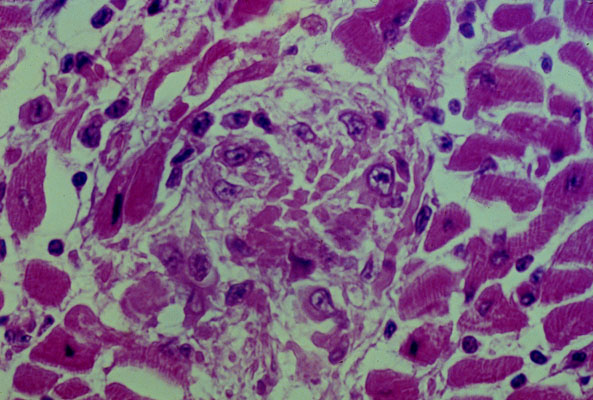

Rheumatic

myocarditis

, histology. The myocardium contains an

Aschoff body

compose of histiocytes around an area of

fibrinous

necrosis

.